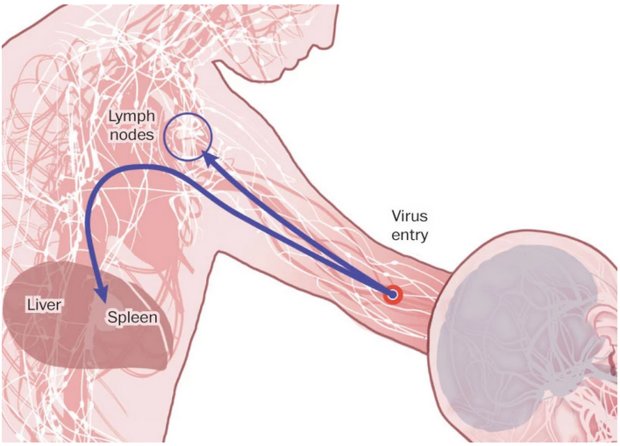

مرحله حمله

ویروس به سلول های ایمنی در جریان خون حمله می کند، و عفونت را به کبد، طحال و گره های لنفاوی انتقال می دهد. ابولا از انتشار اینترفرون، یک پروتئین ساخته شده توسط سلول های ایمنی برای مبارزه با ویروس، جلوگیری می کند.

سلول های ایمنی آلوده از طریق جریان خون یا مجراهای لنفی به دیگر بافت ها و اندام ها، به خارج از طحال و گره های لنفاوی، انتقال می یابند.